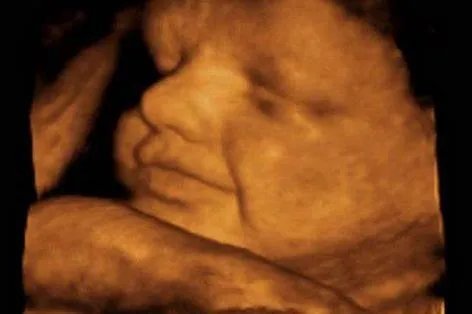

22周左右四维彩超图片c.怀孕26周左右可以做第三次检查这个时期的胎儿皮下脂肪更多,面部表情也更丰富,胎儿各个部位也更清晰。不仅对上述畸形的诊断更加清晰,而且胎儿的面部畸形如吃手指、喝羊水、打哈欠、哭闹等都清晰可见。

26周左右四维彩超图片检查项目a.脑畸形可排除无脑儿、脑积水、脊柱裂、脑膜膨出等脑畸形疾病。b.面部畸形重点观察胎眼与眼眶是否等长,测量两眼间距,详细观察软腭、硬腭,上唇弧形曲线是否连续或间断,主要筛查兔唇畸形。c.脊柱畸形检查脊柱发育是否正常,有无弯曲或中断部分等异常情况。d.心脏畸形此检查可在30周左右进行,排除胎儿心脏畸形,如先天性心脏病、四心腔等。e.泌尿系统畸形四维彩超可以观察胎儿泌尿系统发育有无问题。f.内脏发育不良可查腹部异常、胃部异常、肠道异常,如脐膨出、肠闭锁、巨肠结,以及是否有肾积水、肾虚、多囊肾、膀胱畸形等。预约a.孕妇可以到进行四维彩超检查的医院,当面预约并直接缴费,按照预约的时间及时就诊。b.开通了网上挂号的医院,孕妇可以通过医院的网上挂号系统预约。c.已开通电话预约的医院。孕妇可以打医院客服电话预约。通过网上预约或电话预约进行四维彩超检查。去医院需要说明预约情况,缴费并及时核实信息,然后挂号排队做四维彩超检查。根据地区而变,每个医院预约方法不同。注意事项a.注意时间。要确定四维彩超的检查时间,因为可以提前预约做四维彩超。因为四维彩超检查时间会比较长,大概半个小时左右,所以可以提前预约,按照规定的时间去。如果不提前预约,可能要等半天或者往后推几天,这样会影响当天的检查效果,提前预约。四维彩超检查时间会比较长,医生会花很多时间观察胎儿是发育正常还是有缺陷,所以这也是时间长的原因。b.妊娠四维彩色多普勒超声检查。怀孕期间,四维彩超的孕期也很重要,因为每个阶段做的检查都会不一样。如果怀的是单胎,检查的最佳时间在22-28周,如果怀的是双胞胎,检查的最佳时间在20-22周。要根据不同情况选择合适的方法,切不可错过最佳检查时机。c.保持良好的心态。做彩超时,女性要保持良好的心态,因为有些孕妇可能是第一次做四维彩超检查,难免会产生焦虑或紧张情绪。希望孕妇能调整一下,因为在检查的时候,医生也会根据不同患者的身体进行检查。四维检查,彩超时间会比较长,要及时调整,及时保持心态。此外,选择合适的服装也很有必要。做四维彩超的时候,尽量选择比较舒适的服装,因为做检查的时候会比较方便。综上所述,四维彩超检查是监测宝宝健康最先进的方法之一,可以排查胎儿脑畸形、面部畸形、脊柱畸形、心脏畸形等,一般怀孕14周左右可以进行第一次检查。